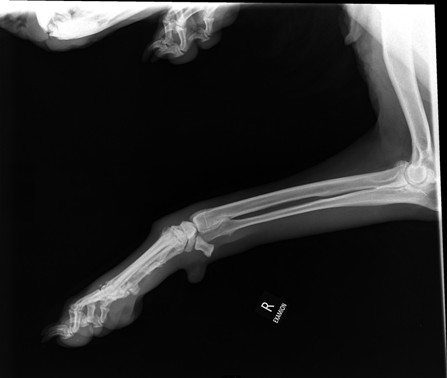

Ania hatte uns darum gebeten, mit Dario zur Klinik fahren zu dürfen, da er Probleme mit einem dicken Gelenk am Hinterlauf hatte. Am 12.01.17 war Ania mit ihm in der Tierklinik,

wo er untersucht und geröntgt worden war. Die Röntgenaufnahmen haben leider ein stark vergrößertes Herz gezeigt, sowie den Verdacht auf Knochentumor ergeben. Zur Sicherheit

wurde ein weiterer TA konsultiert, der die Diagnose leider bestätigte und zudem auch noch

einen Lungentumor diagnostizierte. Die Ärzte rieten dringend zur Euthanasie.